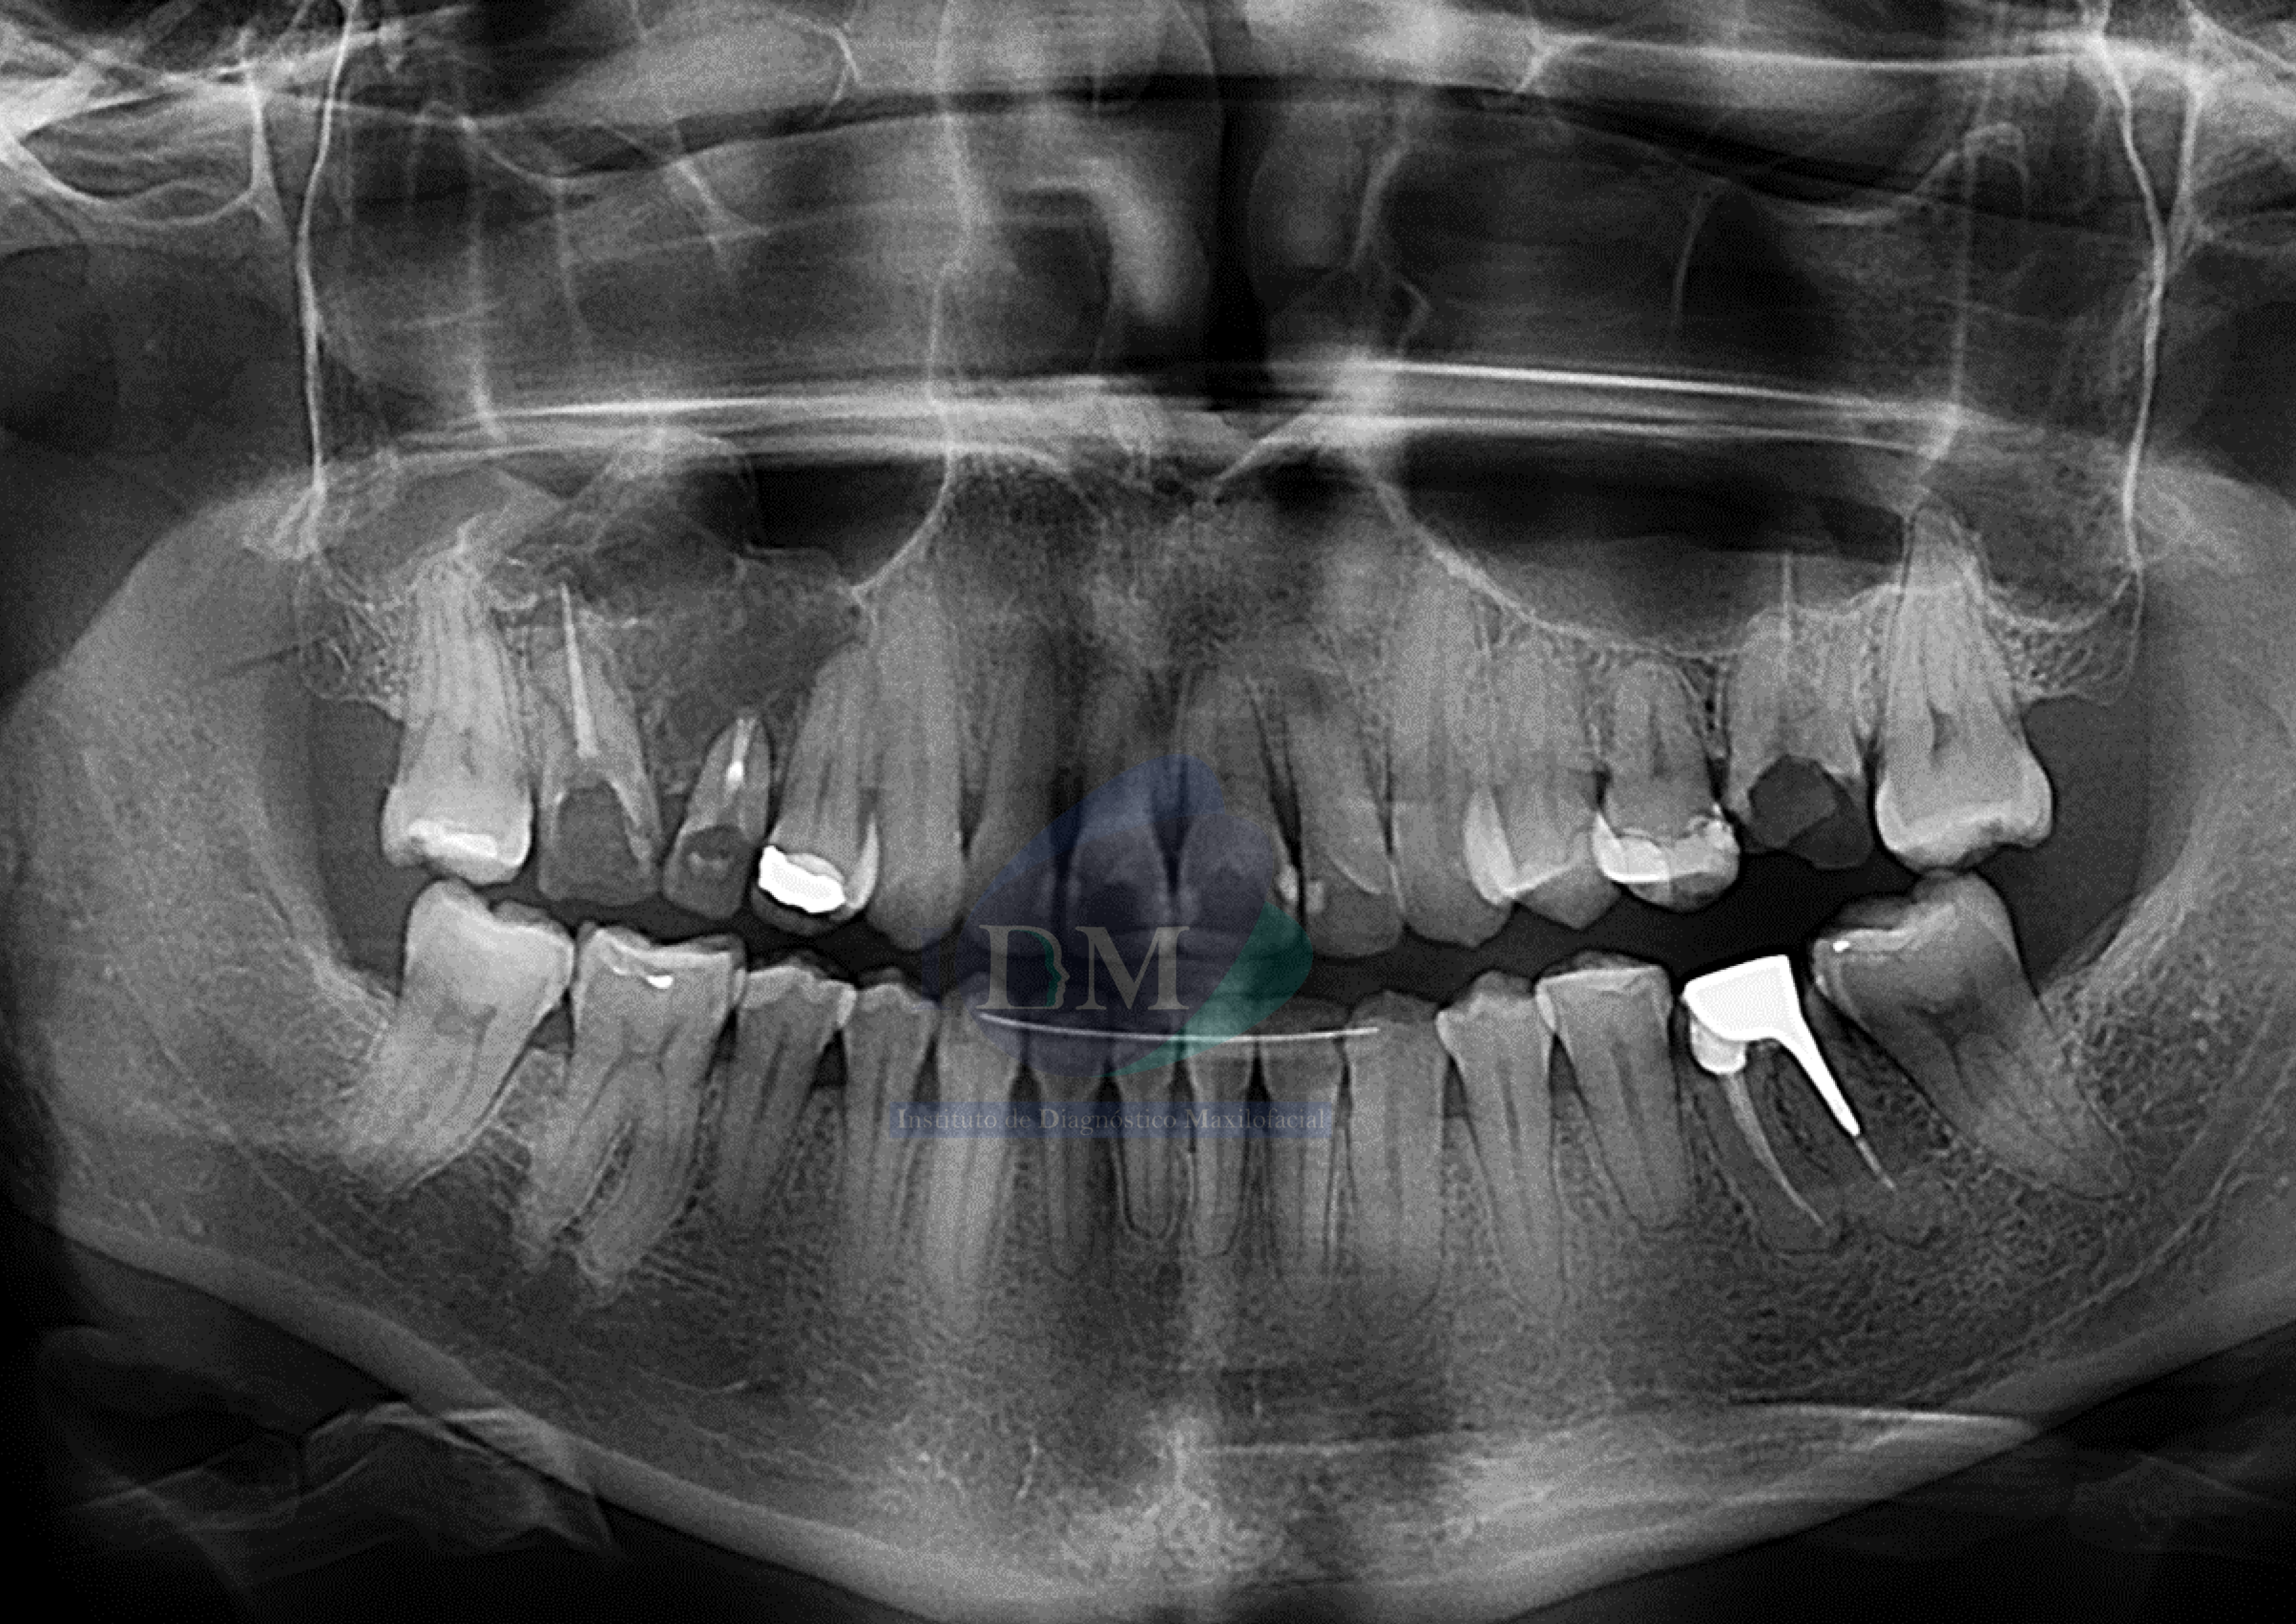

Paciente femenino de 34 años acude al Instituto de Diagnóstico Maxilofacial (sede Miraflores) para evaluación de zona nasomaxilar de lado derecho.

Radiografia Panorámica

A la evaluación de la radiografía panorámica una imagen radiolucida en zonas nasomaxilar derecha, de límites definidos y bordes parcialmente corticalizados. Comprometiendo ambas tablas óseas y piso de seno maxilar.